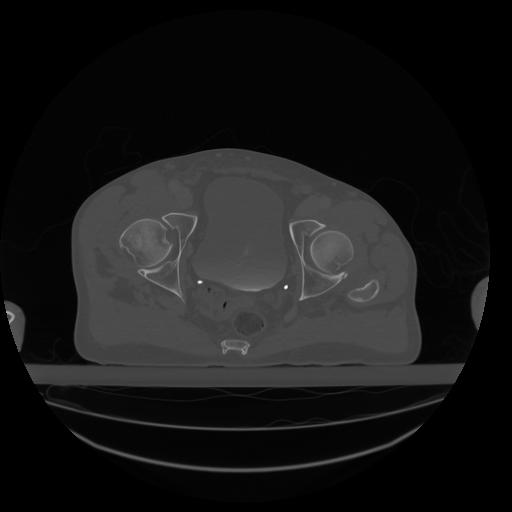

34 CUERPO,CE,Vol,1.0,CUERPO,,